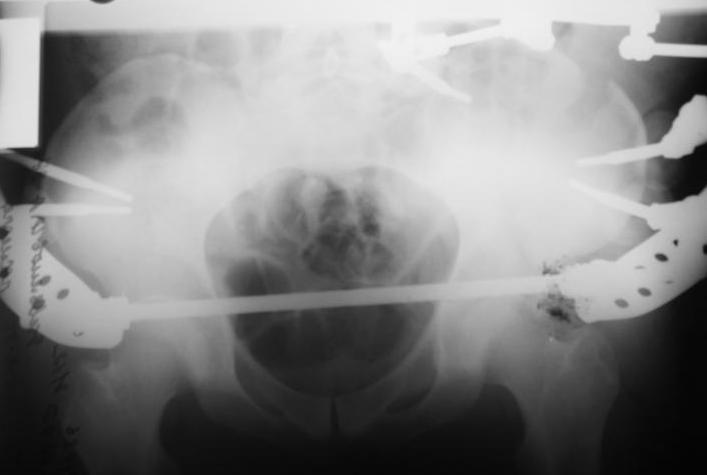

Поступил пациент после кататравмы (упал с высоты 4м). После обследования установлен Ds: Сочетанная травма. ЗТГК перелом 5-6 ребер справа. Ушиб левого леогкого. Оскольчатый перелом крыла подвздошной кости слева, со смещением. в экстренном порядке выполнена операция о/синтез таза стержневым аппаратом. Снимки прилагаются. Пациент со 2-го дня стал ходить без костылей. Из анамнеза жизни у пациента имеется гепатит В и С, с 1998г. употребляет наркотики (героин 1г в день нормальная доза). На контрольных снимках таза в аппарате смещение отломков сохраняется, да еще и стержни сломались. Подскажите ув.коллеги, как поступить в данной ситуации: оставить все как есть или добиваться репозиции в аппарате, или планировать на открытую репозицию. На сегодняшний день пациент стабилен, по анализам компенсирован. Принимает героин по другому справиться не может. С ув. Андрей